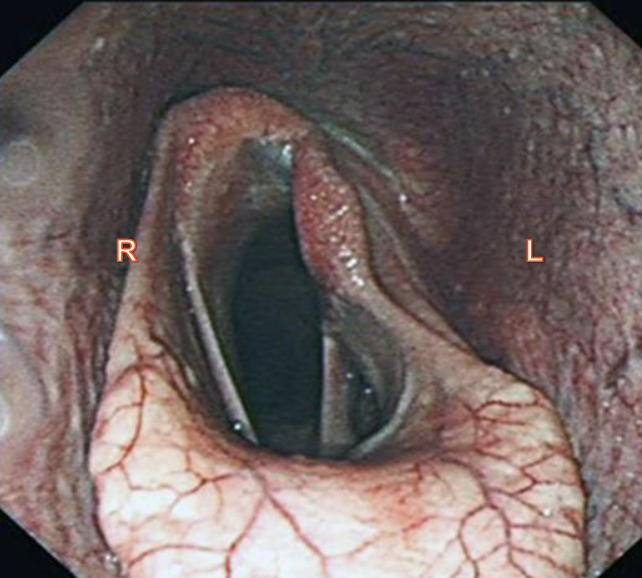

larynx endoscopic view

arytenoids, aryepiglottic fold, vocal folds, laryngeal saccule, epiglottis

laryngeal hemiplagia

half paralysis

aBduct- to move away from midline done by dorsal cricoarytenoid muscle (innervated by left recurrent laryneal nerve)

aDduct- move towards middline